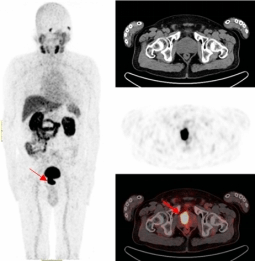

既无肉眼血尿,又无排尿异常,更没有腰酸背痛,但多次血PSA结果异常。患者遂来到PA视讯附属医院核医学诊疗中心接受了68Ga-PSMA-PET/CT检查,结果显示前列腺的确存在良性增生,在结合PET/CT核素影像诊断进行靶向穿刺精准定位后,最终确诊为前列腺腺癌。

前列腺一旦发生癌变就会特异性表达前列腺特异性膜抗原(PSMA),其作为近年来国际上最新的靶向前列腺癌的分子靶点,68Ga-PSMA PET/CT对于前列腺癌的检测在敏感性、特异性、阳性检出率上均高于传统检查手段,对原发灶和转移灶检出率可达到95%,对前列腺癌精准地早期发现、早期诊断,让患者少走弯路。